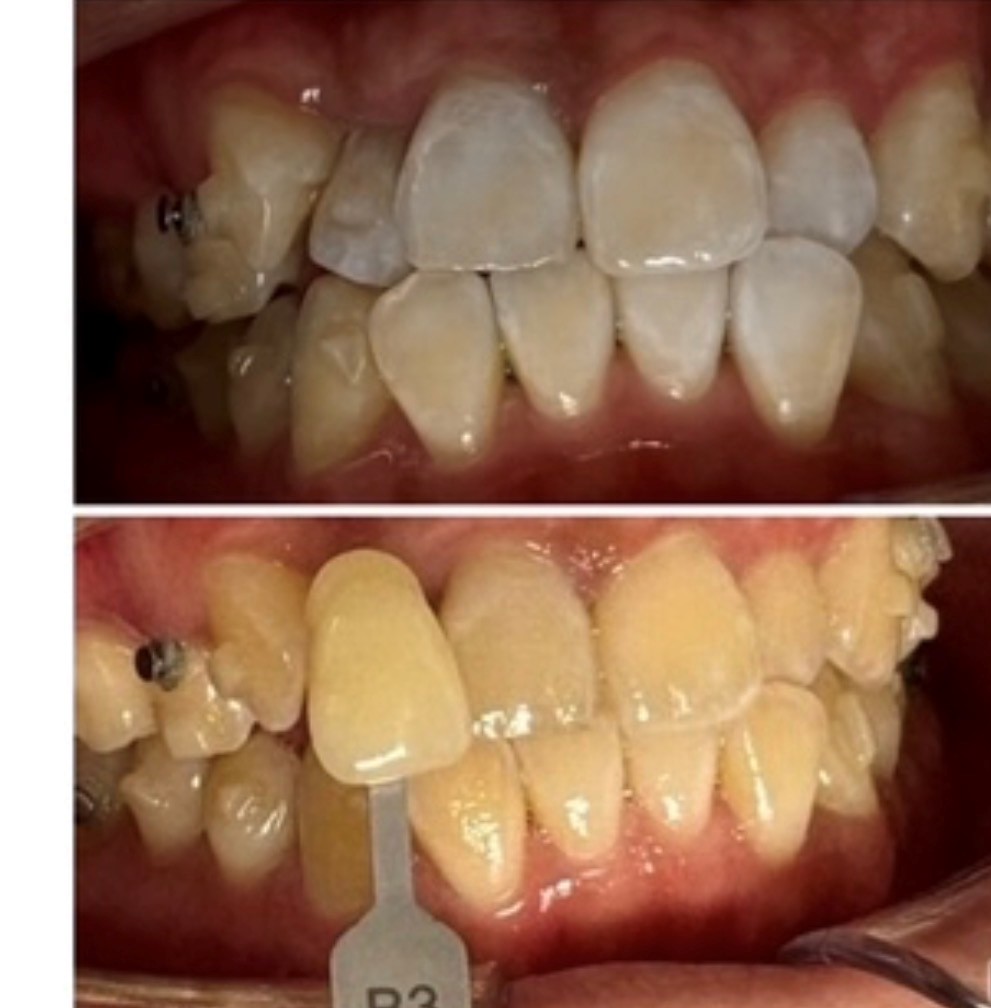

症例画像

治療期間 1回(7分×10分×10分)

治療費用 9800

主訴 歯の着色

治療内容 オフィスホワイトニング

副作用リスク→知覚過敏のようなしみ、痛み。アタッチメントの下の色むら